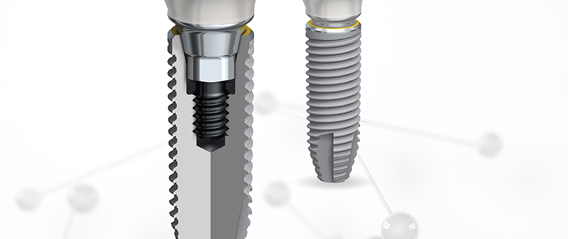

- ITI

士卓曼 - Nobel

诺贝尔 - Hiossen

皓圣 - Osstem

奥齿泰 - Dentium

登腾

口腔种植协会(ITI)推荐的牙种植系统,公认稳定系统。

口腔种植领域的先行者,第一颗种植牙生产者。

美国种植体安心认证:FDA认证的美国种植体,安心更放心。

奥齿泰公司(OSSTEM)近些年研发而成,价格便宜受到用户的青睐。

美国FDA,欧盟CE在内的国内广泛认证。